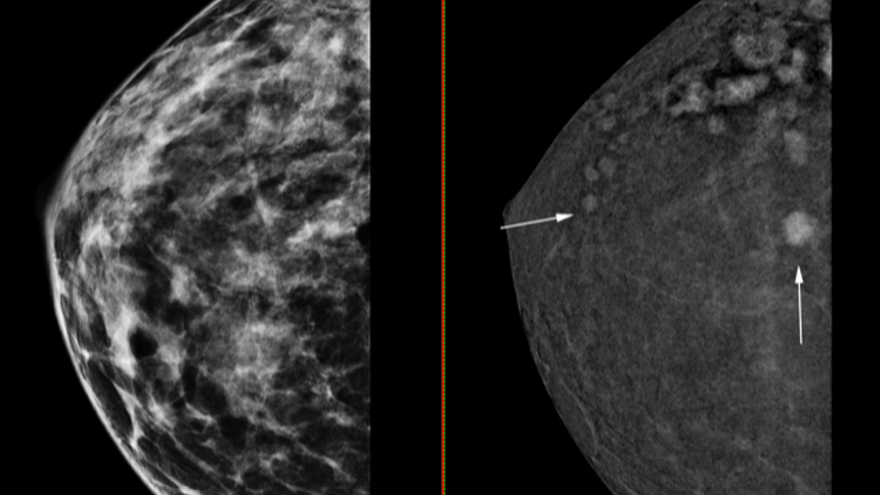

El Hospital del Vinalopó de Elche ha incorporado a su área de Salud de la Mama un nuevo mamógrafo en 3D que es capaz de detectar tumores de tan solo cuatro milímetros, lo que permitirá aumentar un 30% más de casos en fase temprana, mejorando el pronóstico de las pacientes. Así lo anunció ayer el centro hospitalario en un comunicado, detallando que este mamógrafo funciona mediante un sistema en 3D con contraste, que ya está funcionando. El nuevo aparato, además, permite realizar biopsias por tomosíntesis. Esta mejora en la capacidad a la hora de detectar tumores tan pequeños ayudará a mejorar la respuesta en cuanto a tratamientos y a evitar que el tumor se expanda.

La jefa del Área de Salud de la Mama de Ribera Salud, Julia Camps, explicó que «la sensibilidad de esta técnica se acerca al 100%, y es muy similar a la resonancia magnética». Hasta ahora, «a una paciente con antecedentes de cáncer de mama en su propia historia clínica se le hacía una mamografía convencional en las revisiones y, en algunos casos, muy pocos, una resonancia». Con el mamógrafo 3D con contraste «damos a las mujeres que han tenido un cáncer de mama las máximas garantías de que no ha aparecido ninguna otra lesión, por pequeña que sea». En definitiva, «es un cribado muy fiable para las pacientes con más riesgo», concluyó.

La máquina ayuda con las biopsias, tiene la precisión de una resonancia y detectará un 30% más de casos en fase temprana

Hasta la fecha, se han realizado más de 800 pruebas diagnósticas con los mamógrafos 3D en los hospitales que Ribera Salud tiene en España, ya que también se ha incorporado esta tecnología en el de Torrejón. A raíz de esa experiencia explican su importancia, ya que ha permitido detectar lesiones tumorales que no hubieran sido visibles con otro tipo de tecnología.